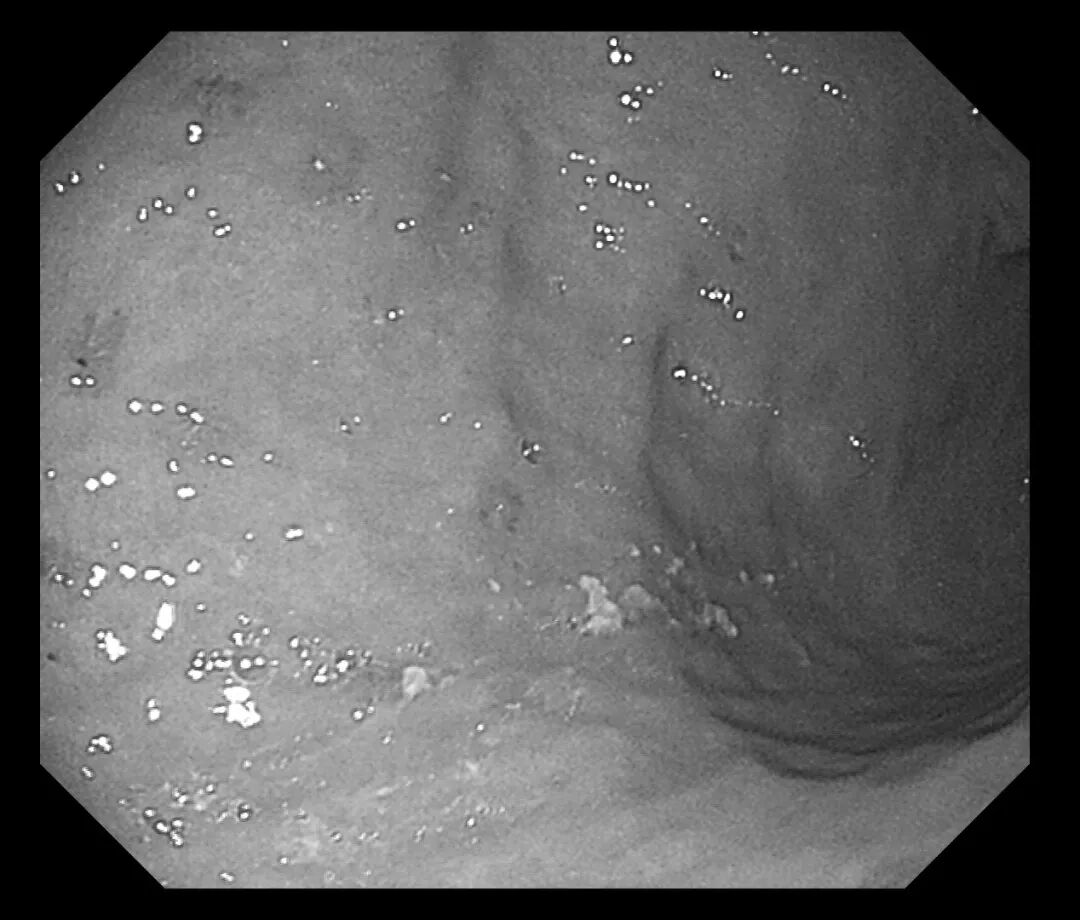

接诊医生刘润萍详细询问病史后,敏锐地意识到这可能是一例典型的“药物性胃溃疡”病例。为明确诊断,在评估患者情况后为其安排胃镜检查。检查结果令人大为震惊:胃窦、胃体等多处黏膜可见十余个直径0.3-0.5cm不等的溃疡灶,部分表面覆有白苔,周围黏膜充血水肿明显。结合患者近期用药史,考虑为“非甾体抗炎药相关性胃溃疡”。

(胃体溃疡)